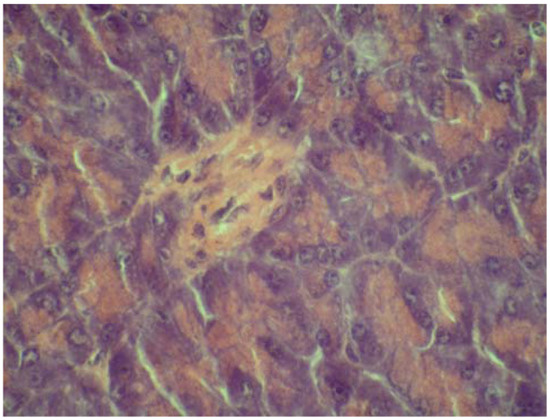

2.4. Cytoprotective effect against alloxan-induced diabetes

3.7. Cytoprotective effect against alloxan-induced diabetes